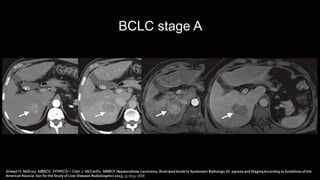

BCLC stage A

Sinead H. McEvoy, MBBCh, FFRRCSI • Colin J. McCarthy, MBBCh Hepatocellular Carcinoma: Illustrated Guide to Systematic Radiologic Di- agnosis and Staging According to Guidelines of the

American Associa- tion for the Study of Liver Diseases RadioGraphics 2013; 33:1653–1668